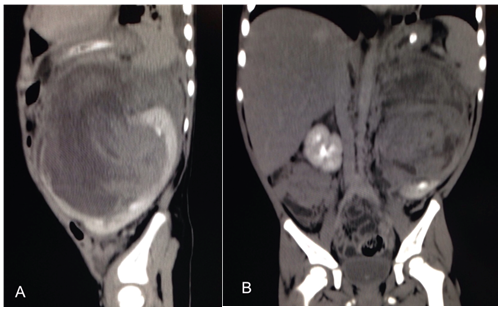

We report the case of a 3-year-old female, with no past medical history. She was admitted to the emergency room after one week left flank pain associated with nausea and vomiting for the last 24hours. Her mother reports that a week before she tripped hitting the floor in the left upper quadrant, with minimal pain in this area until the last 24hours. Physical examination did not evidence hematoma or skin excoriations; we found abdominal bloating, lack of peristalsis and severe pain on palpation in the left flank. Laboratory tests were performed reporting no microscopic hematuria, creatinine 0.8mg/dl, hemoglobin 6mg/dL and hematocrit of 19%. Abdominal computed tomography: left renal hematoma that does not allow the display of spleen, with lower extension and displacement of bowel loops, with no involvement of renal hilum (Figure 1A). Within the hematoma, a 12.8x9x7cm solid lesion with heterogeneous areas located up to 68 UH was identified (Figure 1B). The patient was hemodynamically stable but with persistence of pain and intestinal obstruction secondary to hematoma compression. Clinical presentation with signs and symptoms not according to trauma mechanism and CT scan reports made us suspect the presence of a tumor in the affected kidney. Therefore abdominal exploration was performed; renal hematoma and grade III kidney injury with rupture tumor were found. Left nephrectomy is decided at that time (Figure 2A).

Figure 1 A) TAC with left renal hematoma with lower extension and displacement of bowel loops, without involvement of the renal hilum. B) Coronal view with a left kidney heterogeneous lesion under the hematoma.